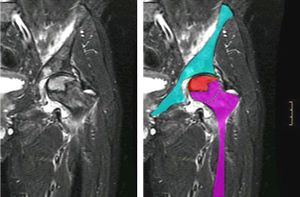

Avascular necrosis of hip

- Plain XR is poorly sensitive in early stages, as low as 41%

- MRI ~90% sensitivity and specificity

- Best test